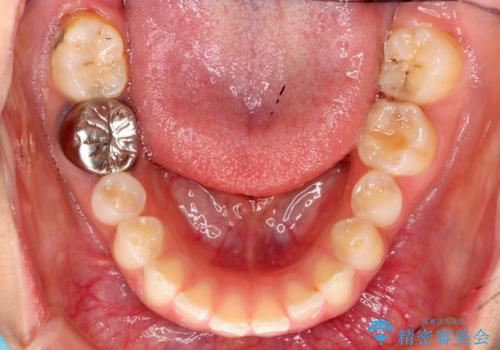

出っ歯を治したい 過蓋咬合

- 出っ歯を主訴に来院。

かみ合わせが深く、治療に時間がかかりました。

上顎2番は矮小歯だったのをセラミックで被せています。